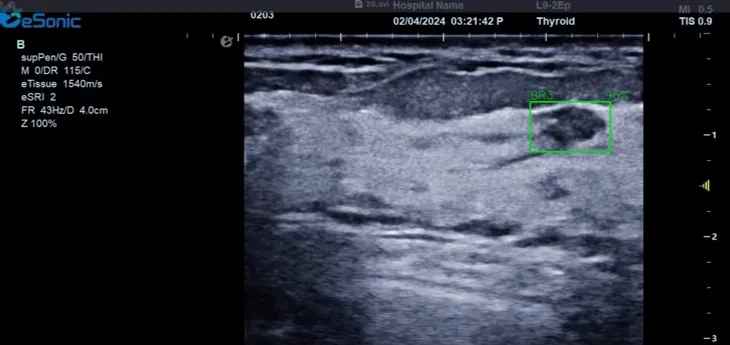

百乐博平台医疗(ESI)表示,其最新的人工智能功能可以帮助到医疗机构的工作效率,功能包括,实时、动态、快速自动识别病灶,良恶性病灶概率预测,甲状腺结节和乳腺的二维灰阶动态自动实时检测需求,提供多个结节动态检测轮廓框。实时获取多幅具备临床特征(大小、属性等)的结节切面,同时提供当前切面所示结节的结节大小、属性特征、TI-RADS 分级。

对于甲状腺结节相关的自动检测功能,甲状腺结节病灶检出率≥95%,良恶性分类灵敏度≥90%、良恶性分类特异度≥85%。